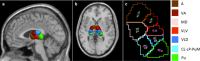

The thalamus is an essential relay station in the cortical-subcortical connections. It is characterized by a complex anatomical architecture composed of numerous small nuclei, which mediate the involvement of the thalamus in a wide range of neurological functions. We present a novel framework for segmenting the thalamic nuclei, which explores the orientation distribution functions (ODFs) from diffusion magnetic resonance images at 3 T. The differentiation of the complex intra-thalamic microstructure is improved by using the spherical harmonic (SH) representation of the ODFs, which provides full angular characterization of the diffusion process in each voxel. The clustering was performed using the k-means algorithm initialized in a data-driven manner. The method was tested on 35 healthy volunteers and our results show a robust, reproducible and accurate segmentation of the thalamus in seven nuclei groups. Six of them closely matched the anatomy and were labeled as anterior, ventral anterior, medio-dorsal, ventral latero-ventral, ventral latero-dorsal and pulvinar, while the seventh cluster included the centro-lateral and the latero-posterior nuclei. Results were evaluated both qualitatively, by comparing the segmented nuclei to the histological atlas of Morel, and quantitatively, by measuring the clusters' extent and the clusters' spatial distribution across subjects and hemispheres. We also showed the robustness of our approach across different sequences and scanners, as well as intra-subject reproducibility of the segmented clusters using additional two scan-rescan datasets. We also observed an overlap between the path of the main long-connection tracts passing through the thalamus and the spatial distribution of the nuclei identified with our clustering algorithm. Our approach, based on SH representations of the ODFs, outperforms the one based on angular differences between the principle diffusion directions, which is considered so far as state-of-the-art method. Our findings show an anatomically reliable segmentation of the main groups of thalamic nuclei that could be of potential use in many clinical applications.